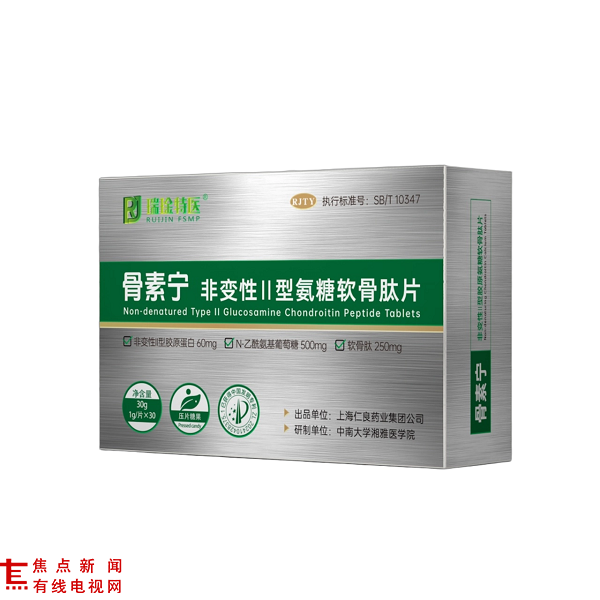

独家专利复配原料,关节健康营养供给再升级

骨素宁非变性II型氨糖软骨肽片的核心优势,在于集结了多种经研究证实的高活性原料,且含量配置远超行业常规标准:非变性II型胶原蛋白(UC-II)60mg /片、N-乙酰氨基葡萄糖(NAG)500mg /片、软骨肽 250mg /片、透明质酸钠 100mg /片,搭配弹性蛋白、乳矿物盐(乳钙)、酪蛋白磷酸肽形成科学复配体系。

其中,非变性II型胶原蛋白通过低温萃取技术完整保留天然三螺旋结构,作为关节软骨核心组成成分,被哈佛医学院研究证实可通过 “口服免疫耐受” 机制调节免疫反应,为软骨修复创造有利条件,其抗炎相关研究效果是传统氨糖+软骨素组合的2.6倍。[1]

N-乙酰氨基葡萄糖作为糖胺聚糖直接前体,无需肝脏转化即可被吸收,吸收率是传统氨糖的2-3倍,是软骨基质合成的关键原料。[2]

透明质酸钠作为关节滑液核心成分,可使关节摩擦系数降低67%,为关节活动提供高效润滑保护。[3]

软骨肽与弹性蛋白的协同作用,进一步完善了关节组织营养供给,多项研究提示该类原料组合对关节软骨保护、炎症因子调节、关节润滑改善具有积极意义。[4]